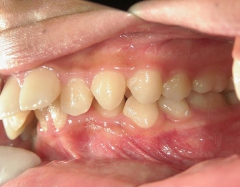

矯正歯科 治療前矯正歯科 治療前

no.18_2196_治療前_右.jpgno.18_2196_治療前_正面.jpgno.18_2196_治療前_左.jpg